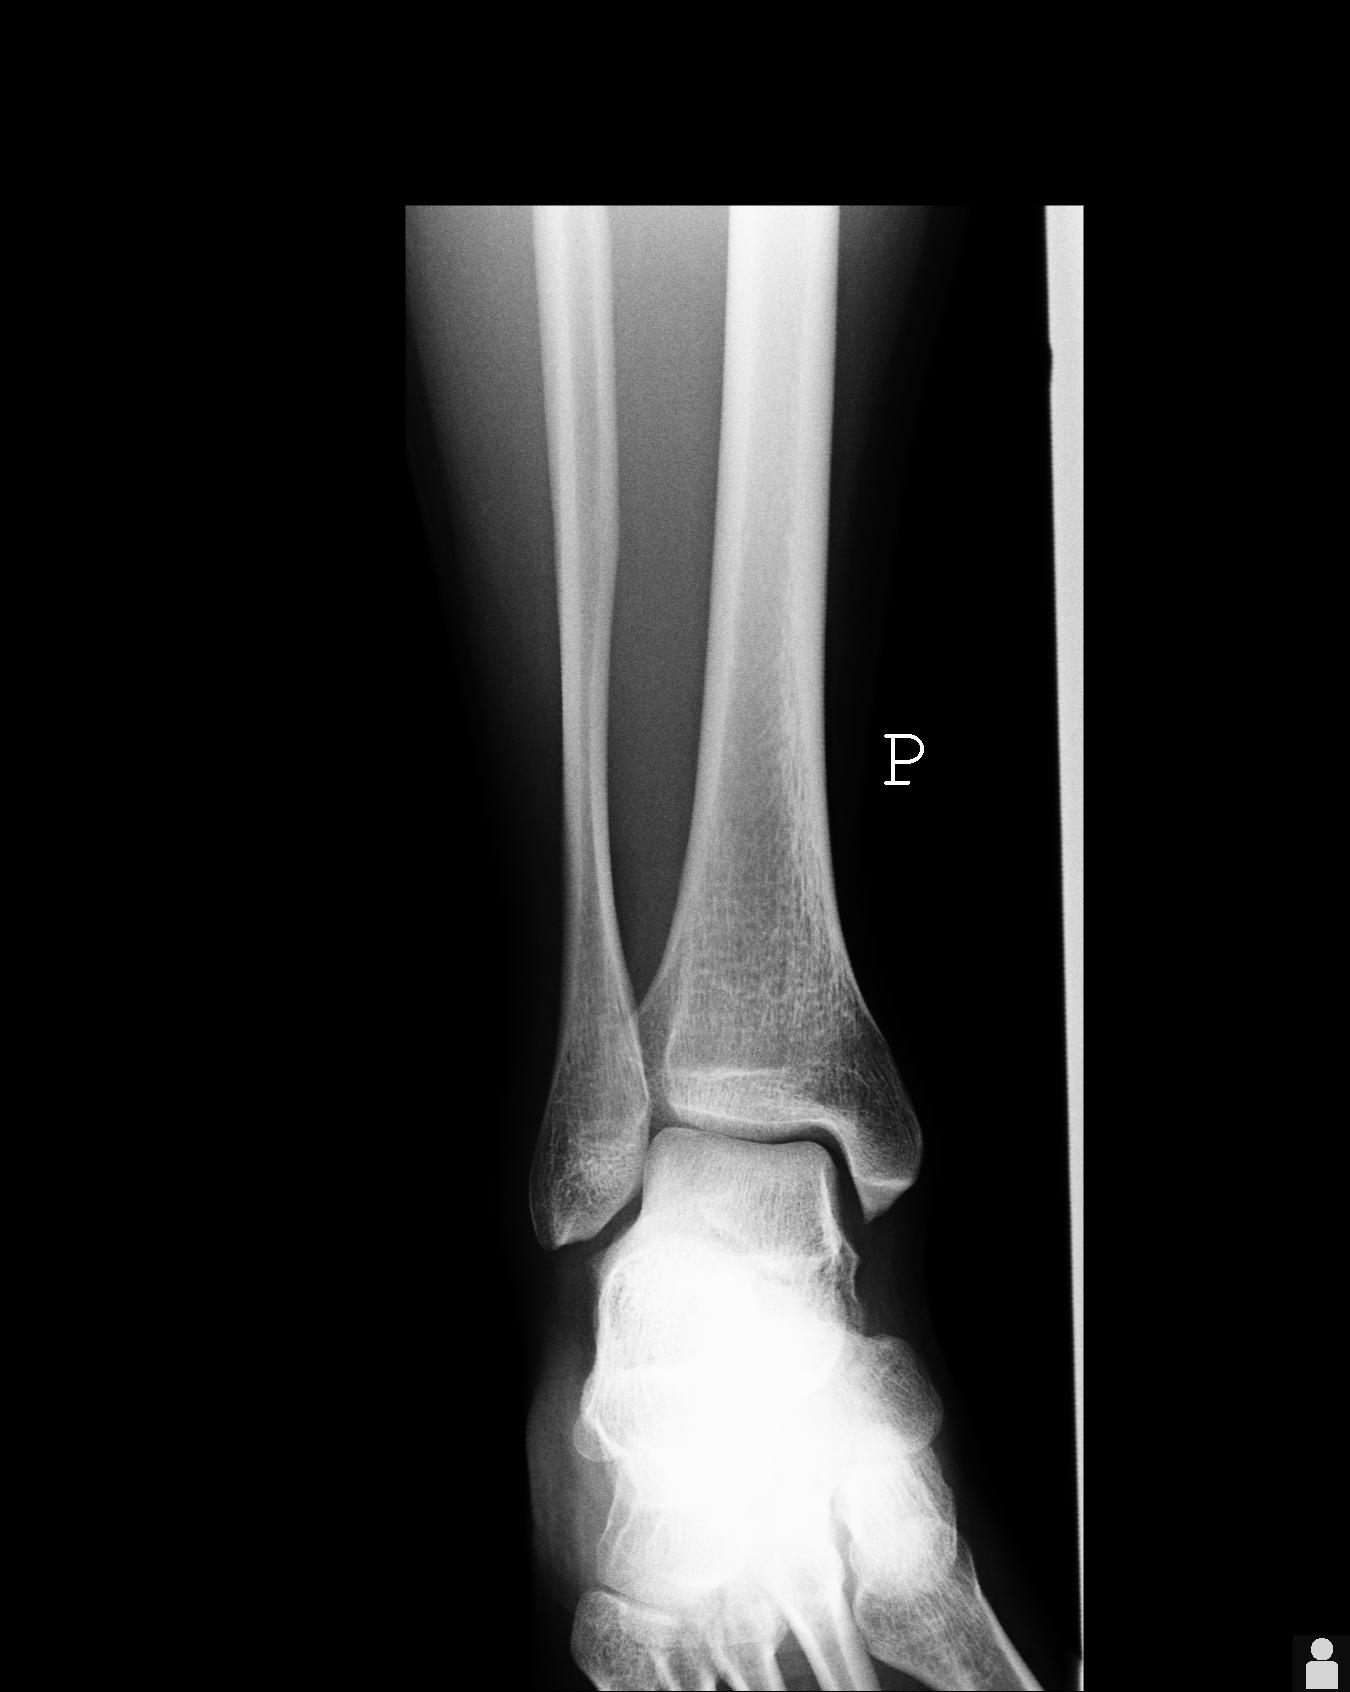

5 tygodni temu doznałem urazu stawu skokowego. Lekarz powiedział, że to nic takiego i po 2 tygodniach będzie dobrze, a ja mam cały czas problem ze stawem. Boli w pewnym zakresie ruchu, jest lekko opuchnięty. Czy ktoś kto ma jakieś pojęcie mógłby zerknąć na zdjęcie RTG?